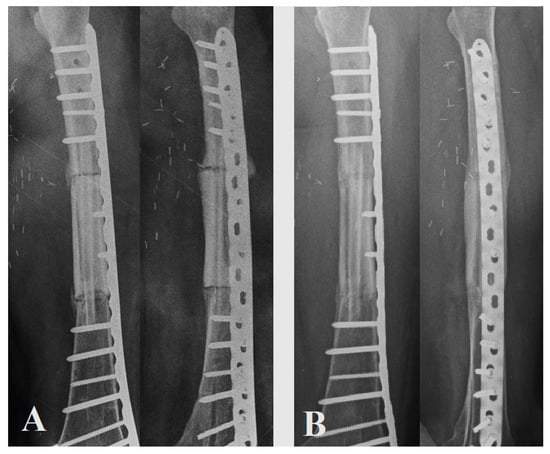

The average time between the two stages was 17 weeks (8–24). Bone union of both interfaces (defined as bridging bone across three of the four cortices evaluated at each junction in the biplane radiographs or CT scan fusion) was achieved at 5.5 months (4–7), except for one irradiated area with a patient who died of their disease. Full weight-bearing was possible at 11 weeks (8–12) in the cohort. Revision surgery was performed for one patient at three weeks for evacuation of a hematoma. Another was performed for stabilization revision (Henderson type 3) on an irradiated area; this patient died of his disease and could not achieve full bone healing due to the pronounced deterioration in their general condition. The functional scores were satisfactory with an EQ5D of 63.3 (45–75) (Figure 4). Patient No. 4 did not obtain postoperative X-rays or CT scans due to the fact of socio-financial difficulties but achieved full weight-bearing at 2 months, with no revision surgery, and was evaluated clinically.

Figure 4.

(A) Control X-rays for patient No. 1 at 3 months postoperatively; (B) control X-rays for patient No. 1 at 10 months postoperatively.